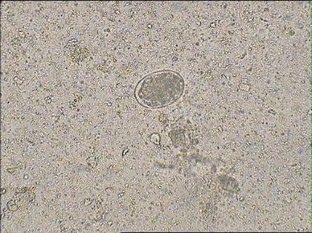

A 3½ years old mongrel female cat was brought with the history of inappetence, seizure and lateral recumbency since 4 days and motion sickness since 2 days. Faecal examination confirmed Toxocara cati and Ancylostoma tubaeforme along with un-hatched live Toxocara cati larvae. Treatment has been initiated with Pyrantel pamoate and along with supportive therapy.

Fig. 1

Fig. 2

Fig. 3